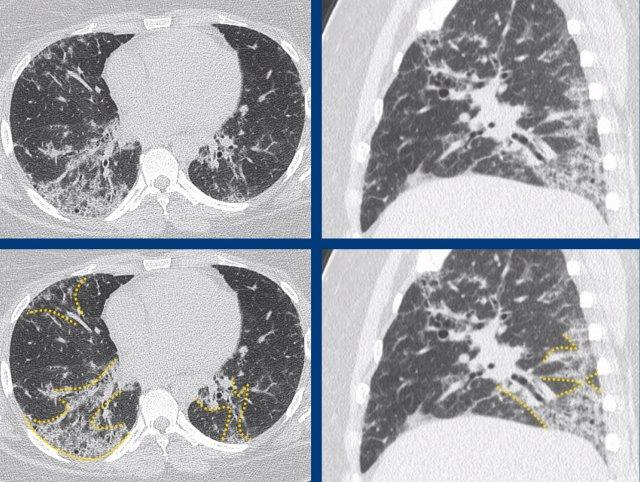

Hình ảnh cho thấy bệnh phổi xơ hóa với sự biến dạng của tiểu thùy thứ cấp, mất thể tích và giãn phế quản do co kéo (màu xanh lá là bình thường, màu vàng là bất thường).

Đầu tiên, xơ hóa phải có gradient hướng về phía đáy phổi, với thùy dưới và góc sườn hoành bị tổn thương nhiều hơn so với vùng phổi giữa và trên.

Các hình ảnh cho thấy tổn thương xơ hóa ưu thế ở vùng đáy phổi và dưới màng phổi trong A, so với tổn thương xơ hóa ưu thế ở vùng đỉnh phổi và trung tâm trong B.

Subpleural dominant (A), subpleural sparing (B), and peribronchial dominant (C) patterns of fibrosis.

Thứ hai, xơ hóa phải có dạng chiếm ưu thế dưới màng phổi. Điều này có nghĩa là bệnh nhắm vào mô kẽ ngoại vi và tổn thương phổi ngay bên dưới màng phổi.

Bệnh không được bỏ qua mô phổi dưới màng phổi, cũng không được tập trung xung quanh bó phế quản-mạch máu (tức là không được tổn thương chủ yếu ở mô kẽ trục).